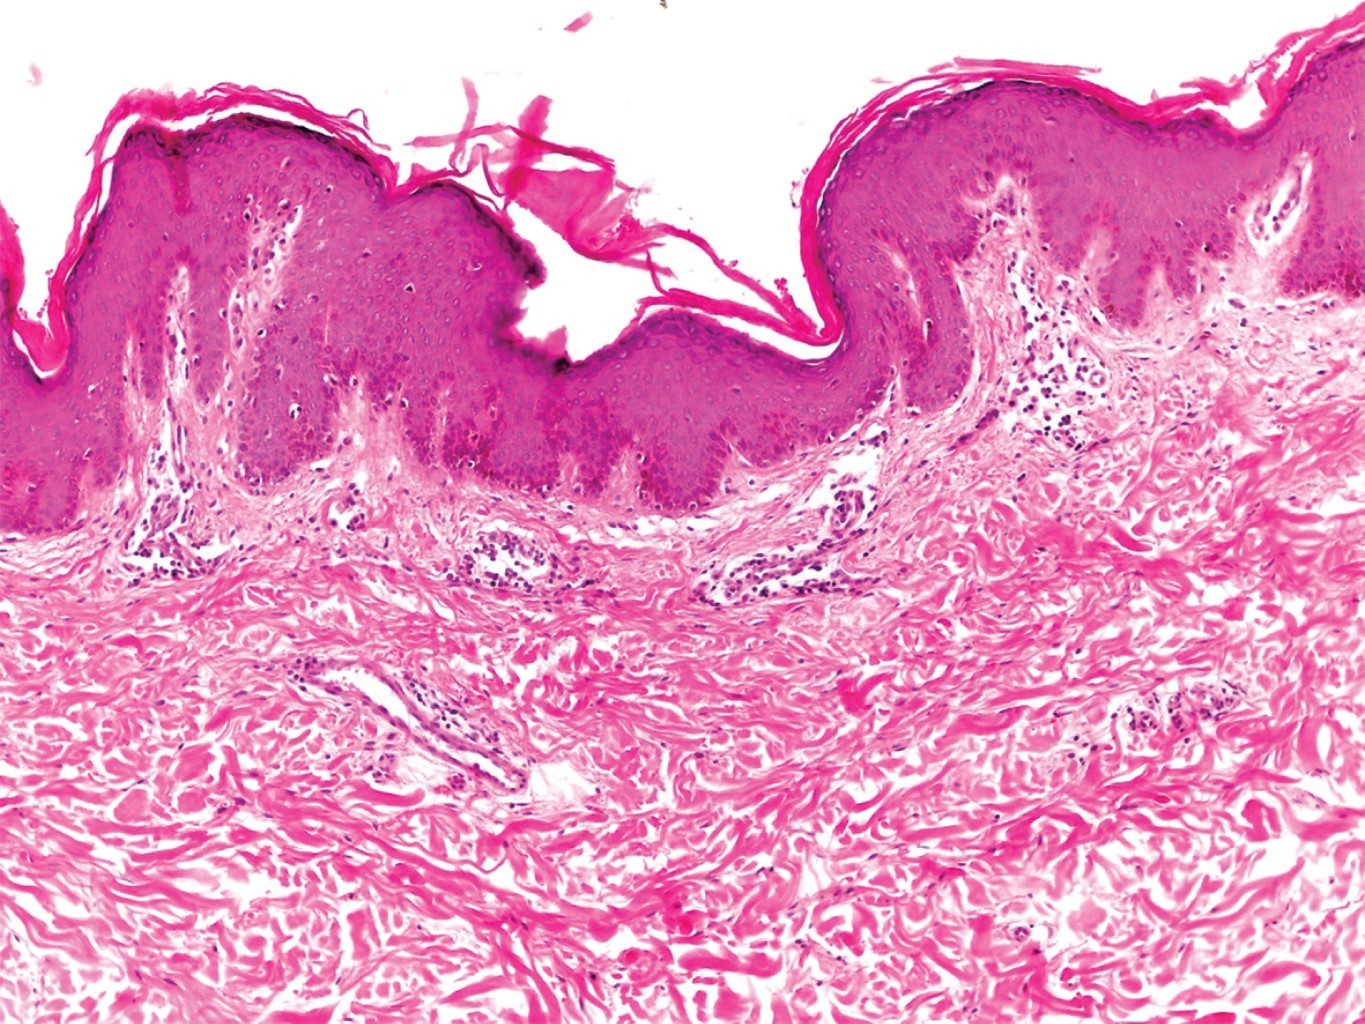

En la variedad superficial pueden observarse cambios epidérmicos de paraqueratosis con espongiosis, con infiltrado denso de linfocitos e histiocitos (y con menor frecuencia, de eosinófilos) alrededor del plexo vascular superficial (Figuras 4 y 5). El edema en la dermis papilar es mínimo. En la variante profunda, el infiltrado invade hasta el plexo vascular profundo. Tiene una disposición característica en "manguito" alrededor de vasos superficiales y profundos; las células pueden extenderse hacia las paredes de los vasos pequeños; sin embargo, nunca se observa extravasación de fibrina; es una pseudovasculitis. La epidermis es prácticamente normal, aunque se han descrito queratinocitos apoptóticos y, ocasionalmente, cambios vacuolares.3 Weyers y colaboradores estudiaron 73 casos con EAC, 50 de ellos con la variedad superficial, y 32 con la profunda. En aquellos superficiales, se observó en 100% infiltrado superficial, 80% presentó espongiosis (que generalmente era focal), así como paraqueratosis en dos tercios de los pacientes. La histopatología de los 32 casos de EAC profundo demostró la presencia de infiltrado profundo, y mínima o ausente paraqueratosis; en 69% de los casos se apreciaron melanófagos.3

Figura 3

Figura 4